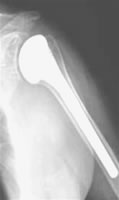

Im Spätstadium der Arthrose mit Aufbrauch des Gelenkknorpels und „Knarren“ sowie Bewegungseinschränkung ist auch hier der Gelenkersatz, d.h. der Einbau eines künstlichen Gelenkes, ähnlich wie an Knie und Hüfte, möglich.